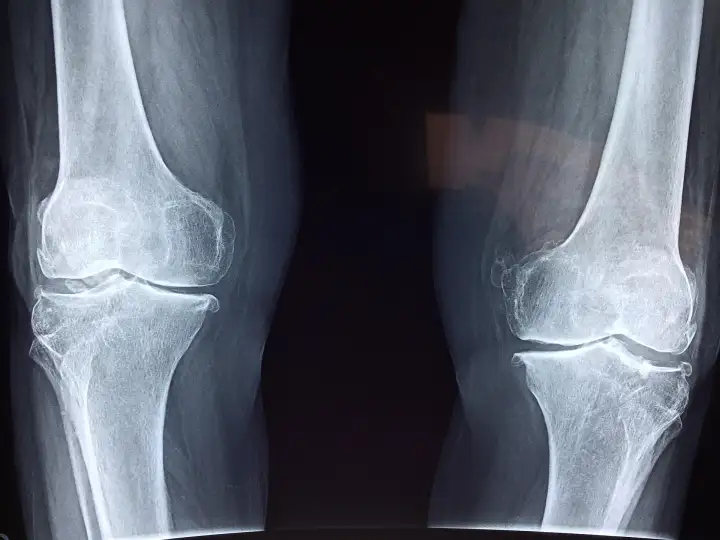

Замена коленного сустава может значительно улучшить качество жизни пациента, если только не разовьётся инфекция. Хотя большинство операций по замене тазобедренных и коленных суставов обычно проходят хорошо, частота постоперационной инфекции может достигать 2%. Поэтому учёные из австралийского Университета Флиндерса создали соединение с жидким металлом, чтобы устранить этот вредный побочный эффект.